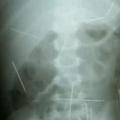

Brazilija V telesu ima 50 igel Dveletnega dečka so zaradi bolečin v trebuhu in bruhanja sprejeli v bolnišnico v brazilski zvezni državi Bahia. Zdravni…